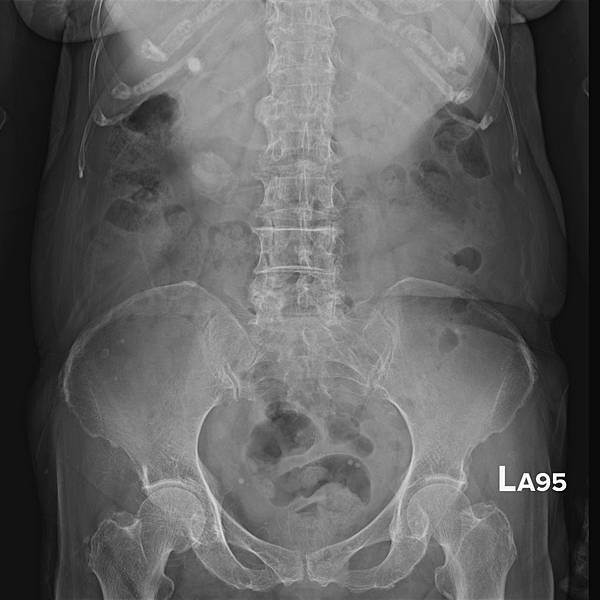

KUB看不出她的病有多嚴重: